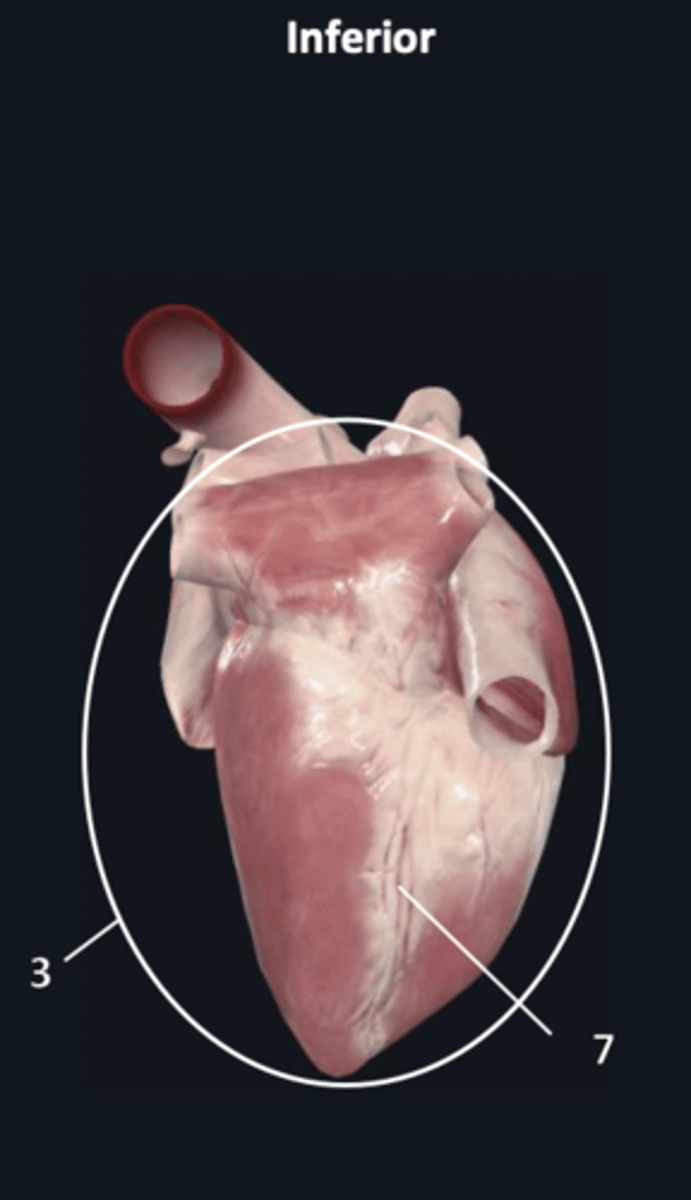

diaphragmatic surface

3

posterior interventricular sulcus

7